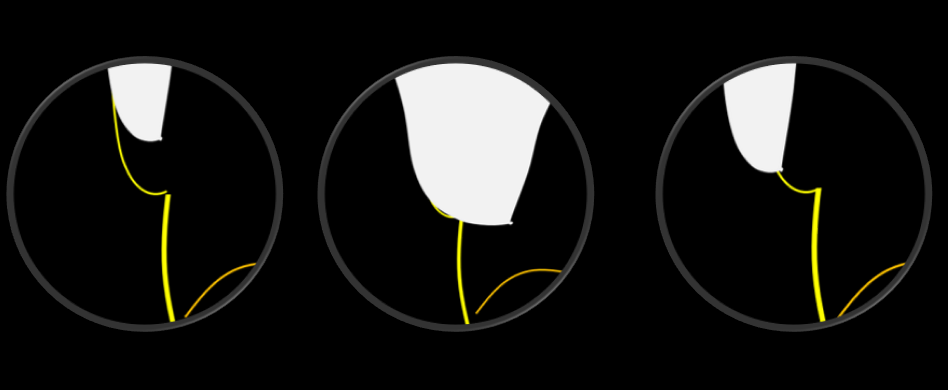

图3. 全冠边缘不良的几种表现示意。